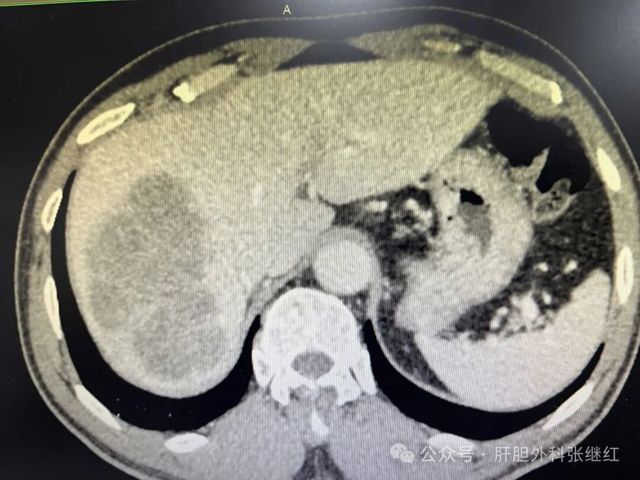

新辅助治疗后前入路右半肝切除术治疗右肝巨大肝癌